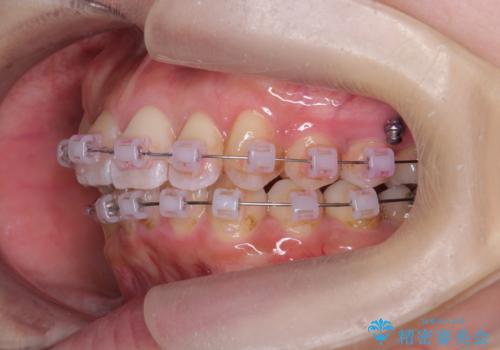

上の歯列を後ろに下げるのに、矯正用ミニスクリューを使用しています(インプラント矯正)

- ワイヤー矯正